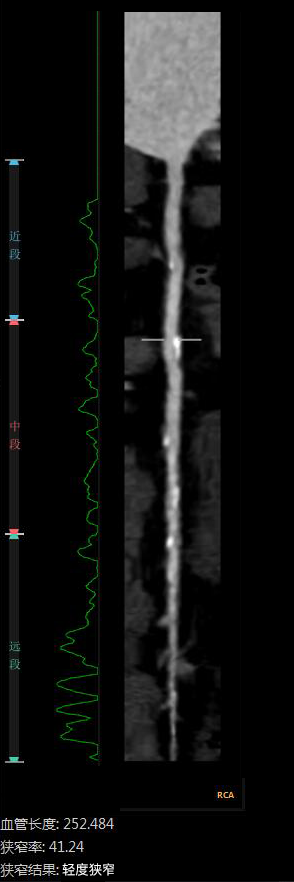

“CTA冠脈全自動(dòng)診斷”

Automatic Coronary Diagnosis

全自動(dòng)圖像重建/分割

全自動(dòng)量化測量

全自動(dòng)結構化報告

云端AI的CTA冠狀動(dòng)脈全自動(dòng)診斷

重構了CTA冠脈檢查的極簡(jiǎn)流程